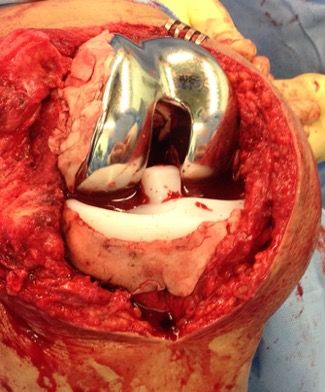

Temporary AB spacer prosthesis

After extensive pulslavage (5 to 9 liters) with normal saline new draping and gloves are necessary. For the temporary spacer prosthesis, we us one size larger standard PS femur and PS 10 mm PE insert fitting to the size of the proximal tibia. Using the trial components, it can be checked if there will be enough space in the flexion/extension gap to allow a thicker cement mantle (Fig 9).

Since we use a modified “all poly tibia without a keel” cement fixation holes are drilled into the backside of the poly insert with the 9 mm sharp drill. Therapeutic AB cement with 3 to 4 g of AB powder is hand mixed with the 40 g of PMMN powder (Fig 10 and Table 3). The AB cement is mixed for the tibia and femur separately and used for implantation once he is a doughy phase.

First the “all poly tibia” is implanted in flexion with full view on the proximal tibia surface. AB cement is but into the prepared keel and on the tibia surface with a layer of 1 cm. Any additional structural bone defect will be filled with AB bone cement. The poly insert is then carefully pressed into the proximal bone cut and the extra AB cement will fill the fixation holes and extrude to edges of the bone (Fig 11).

This extra cement at the edges should now be modulated to achieve an additional circumferential fixation of the poly insert. The cementing technique should be the worst possible to prevent locking with the trabecular bone which will allow easy removal after 6 weeks. This includes using the cement in a doughy phase, no use of tourniquet, bloody and not clean bony surfaces and lifting the whole construct for a few cementers to allow lavage of the cement-bone interface before complete hardening of the AB cement. This allows a “press cementation” and after complete hardening the tibia component might be taken out completely to guarantee that there will be no extra cement posterior (Fig 12).

After the tibia is completely done the femur will be cemented in full flexion by using the same “bad cementing technique” as described before for the tibia. The femur should not be fully seated, and some extra cement mantle should be left. The tibia is now connected to the femur cam will get behind the tibia post without dislocating the tibia or femur component. If you choose a CR tibia insert this maneuver will be less difficult, but you will lose sagittal stability for the AB spacer prosthesis. Balancing and alignment of the spacer prosthesis is now performed by the assistant standing at the end of the table and pulling on the leg and bringing the leg from flexion to full extension. In full extension the alignment should be clinical straight and by forced pulling the extension gap should be stable. Any correction of the alignment or to establish stability can still now be performed by changing the position of the femur and filling the interface with cement. Like at the tibia extra cement should be used to stabilize the edges of the component and before complete hardening of the cement the construct should be lifted in flexion to lavage the interface.

After final hardening the femur component might be taken out completely to prove “press fit cementation” (Fig 11). With the temporary AB prosthesis in place (Fig 13) a final check for proper alignment, ROM and stability in extension and flexion should be checked. If there will be any doubt that the knee is not stable enough a brace should be used for mobilization.